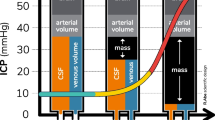

As stated above, IH leads to ICS, but what leads to IH in the first place? The basic concept of ICP is described by the Monro-Kellie Doctrine, which is based on separate studies by the Scottish physician Alexander Monroe secundus (1733–1817) and the surgeon George Kellie (1770–1829). Essentially, the doctrine states that total intracranial volume is constant and fixed although the relationships between its components may vary. Total intracranial volume is determined by the sum of the volumes of cerebrospinal fluid (CSF), blood, and brain tissue. We can roughly estimate that CSF and blood occupy each 10% of the volume, leaving to the brain tissue the remaining 80% (near 1900 mL in adults) [2].

ICP is normally below 10 mmHg, and it is relatively constant through all the brain regions. The introduction of an additional volume in one of the three components must be compensated by changes in the other two components; however, a volume increase of more than 10% leads inevitably to the upper limit of the system’s compliance and so to an increase in ICP. Since the skull is rigid, from this point on, minimal increases in intracranial volume translate into wide increases in ICP (exponential relationship, see Fig. 2.1).

As stated before, the limit of compliance of the intracranial compartment is an increase in volume of about 10%. This means that the brain is not normally able to swell more than 10% of its volume and the same is true for the CSF and the blood component. According to the Monro-Kellie Doctrine, these changes modify the total volume and must be counterbalanced by a correspondent reduction of the other components. Namely, both the CSF and the blood components are able to shift outside the intracranial compartment as explained below. Displacement of CSF and blood explains the horizontal part of the pressure–volume curve represented in Fig. 2.1. Of course, individual patients may show better compensation than others, for example, due to cerebral atrophy, which warrants higher volume reserve by shifting the pressure–volume curve to the right.